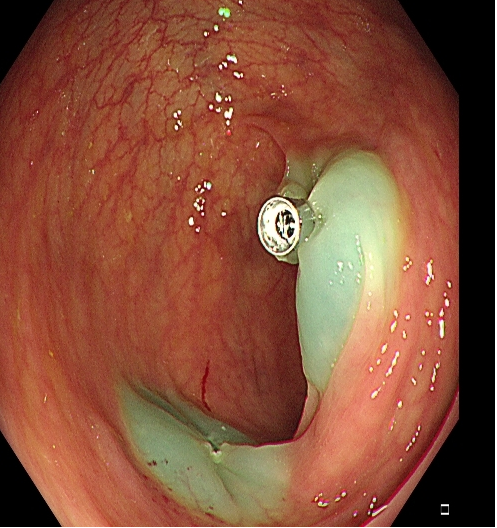

对于大型Ⅰp病变,除以上注意事项外,应采用热圈套方式切除,切除前应于蒂根部充分黏膜下注射(经内镜注射针将2~10 mLl万单位的肾上腺素+亚甲蓝+生理盐水混合液注射于黏膜下,边退针边注射),致使蒂部充分隆起,易于切除(图 3),切除过程中病变应避免接触肠壁,以免形成闭合回路,灼伤肠壁。

需要注意的是大型Ⅰp型息肉若蒂部较粗,则可能含粗大滋养血管,切除后极易出血。切除过程中可采用凝-切-凝的方式,减少出血风险。部分较大息肉,可采取分块切除方式,降低操作难度,但此法不利于病理评估。